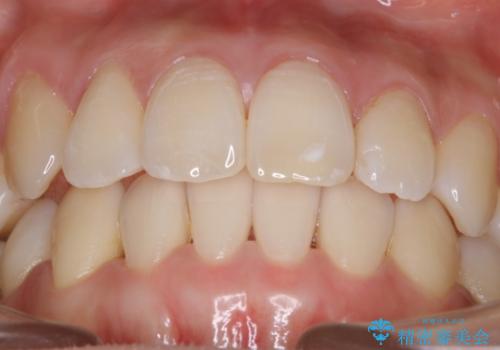

【非抜歯】インビザライン 隠れた前歯を並べる矯正治療

- 前歯のガタつき・奥に隠れてしまっている歯の矯正治療を希望されて初診来院されました。

顔貌的に口元を下げたいといった希望はなく抜歯はなるべく避けたいとのご要望からマウスピース装置(インビザライン)での治療を行うこととなりました。

非抜歯で矯正を行う場合にガタつきの改善に必要なスペースを作るために歯の遠心移動を行います。

最初の位置から奥に歯を移動させていくことで前歯のガタつきを改善したり、前歯の位置を後方に移動させることが可能となります。

その反面、歯の移動距離が大きくなるので治療期間が長くなる傾向があり、その分コントロールの難しさが上がることが予想されます。